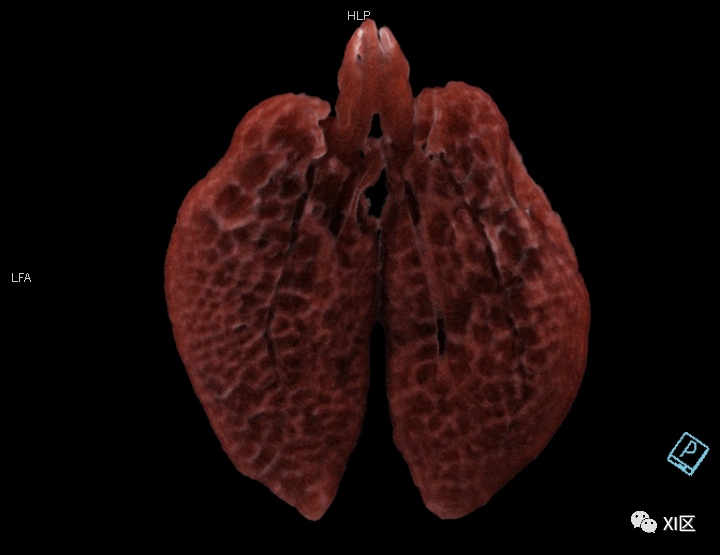

牛蛙肺部重建

第二,

我们仔细观察了牛蛙的肺结构

不同于人类

牛蛙的两肺气管很粗大

直接和声门相连

气出来的更顺利

牛蛙肺部细节

肺部血管分布